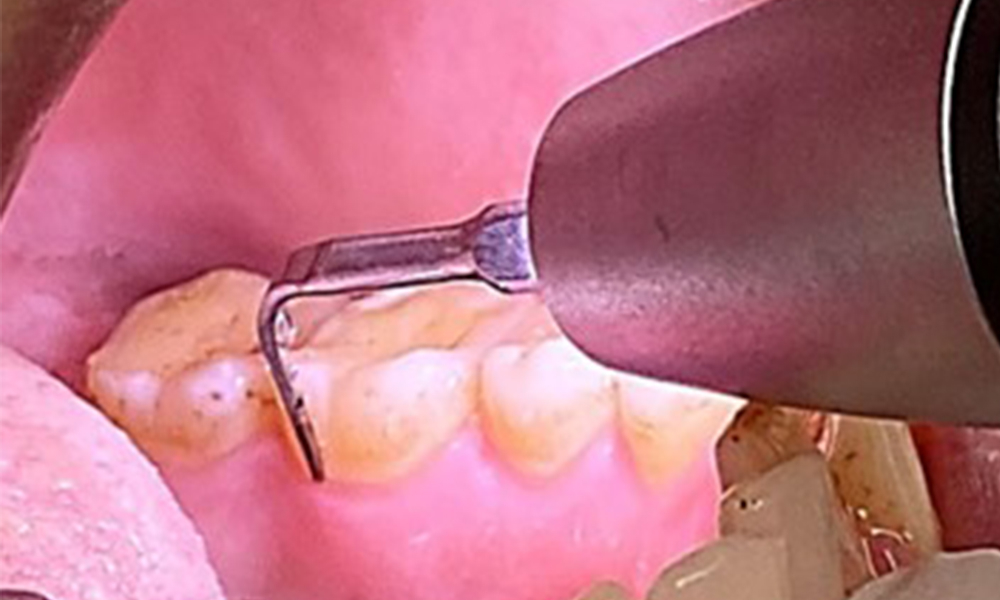

L'objectif serait de contrôler le risque de maladie en éliminant le biofilm supra-gingival et sous-gingival. Les instruments peuvent être sélectionnés en fonction des besoins du patient. Tout d'abord, le tartre et les concrétions doivent être éliminés à l'aide d'instruments ultrasoniques et/ou manuels (Fig. 10).

Utilisation d'un appareil à ultrasons piézoélectrique dans la zone linguale près de 36 (Proxeo Ultra, W&H, illustré ici).

Fig. 10 Utilisation d'un appareil à ultrasons piézoélectrique dans la zone linguale près de 36 (Proxeo Ultra, W&H, illustré ici)., © Dr R. Krapf